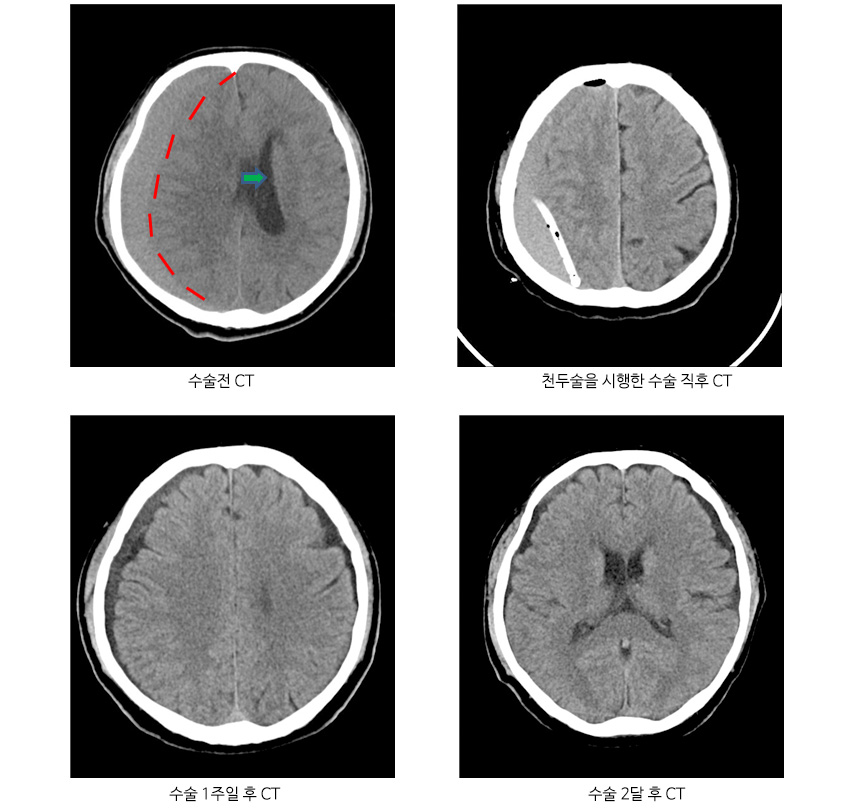

치료는 고혈압성 뇌출혈인 경우에는 혈종의 크기와 환자의 상태에 따라 치료법이 달라지며 혈종 크기가 작은 경우 약물치료를 시행하고, 혈종 크고 마비가 있는 경우 두개골에 구멍을 내서 관을 삽입하여 혈종을 배액시키는 수술법이 있습니다.

자발성 뇌내출혈 CT